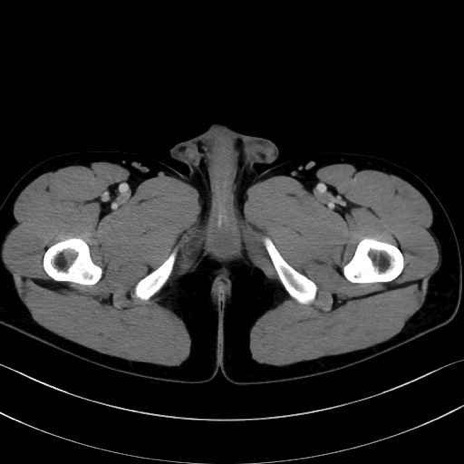

中殿筋(gluteus medius)のCT画像の解剖

中殿筋 (Gluteus medius)